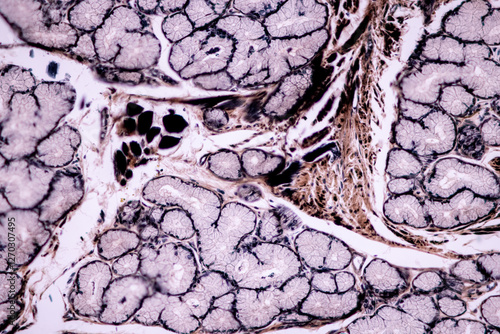

Mikrofotografi - Plakater, Poster, Billeder på lærred